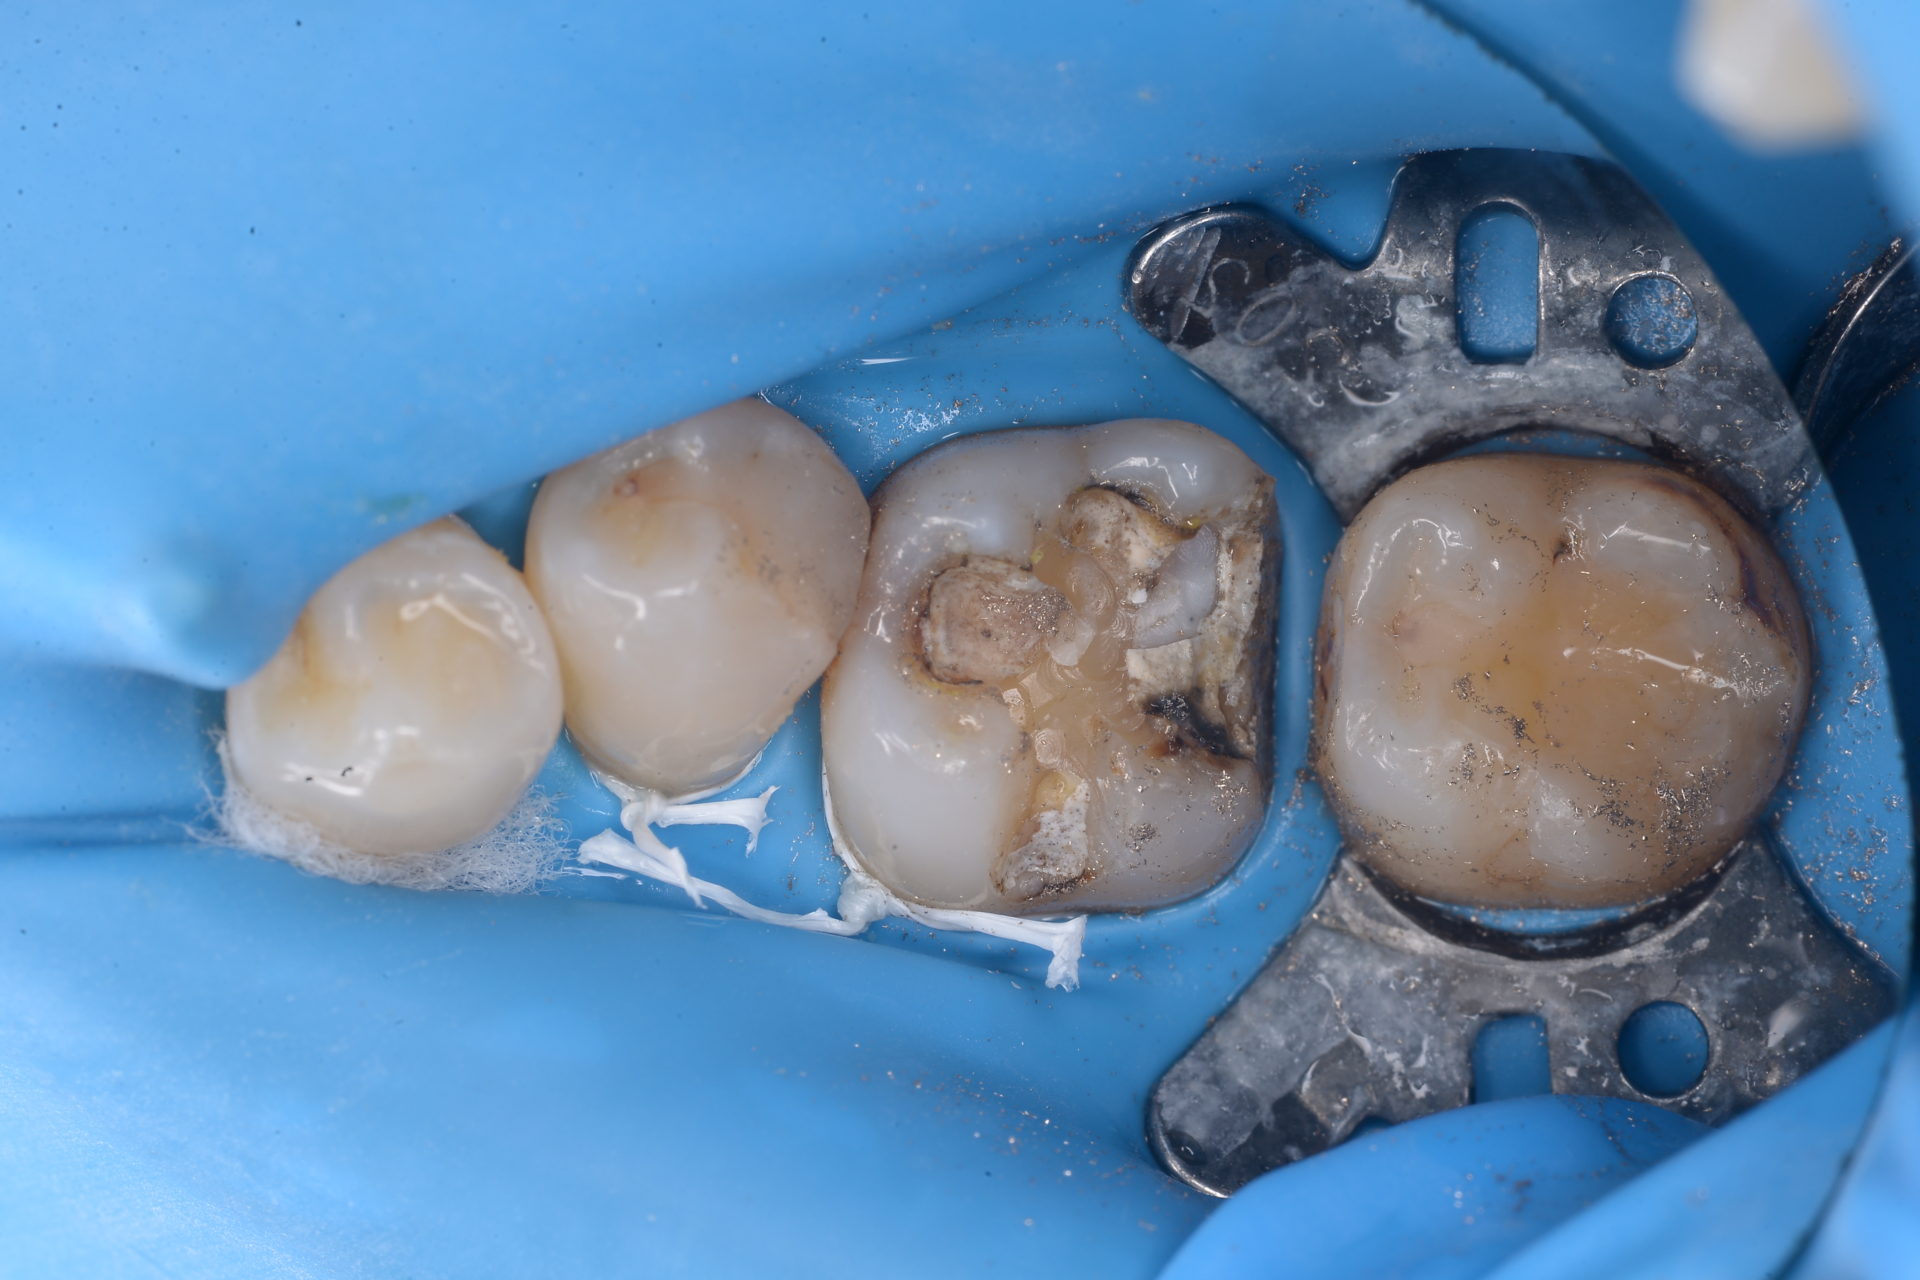

詰め物や被せ物の除去

詰め物や被せ物の除去の際、バキューム(唾液を吸う器具)だけでは削りかすがお口の中に溜まってしまいます。

このように銀歯を外すときは多くの金属粉がでます。身体に害のある金属を飲み込まないようにすることは大切です。

そこで、ラバーダム防湿をすることにより、上記の写真のように削りかすがお口に入るのを防ぐことができます。

特に「アマルガム」と呼ばれる銀歯には水銀が含まれているため、体内に取り込まれないように注意しなければなりません。ラバーダム防湿をすることで、削りかすや外れた詰め物や被せ物がお口の中に入らず、安全に除去できます。